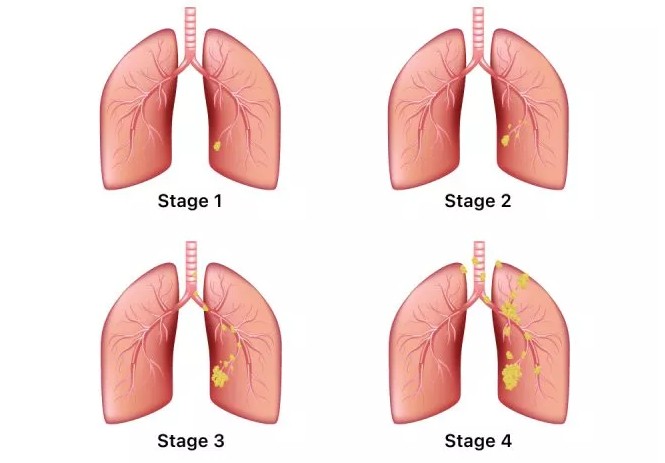

폐암은 초기 자각 증상이 뚜렷하지 않아 굉장히 진행된 상태에서 발견되는게 대부분입니다.. 그렇지만 조기 폐암은 매우 작은 부분만 절제해도 치료가 가능하며 생존율이 70~90%에 이른다.

폐암 증상에는 기침, 체중 감소 흉통, 혈담 즉 피가 섞인 가래, 호흡곤란 등이 있지만, 위 증상은 다른 폐 질환에서도 나타날 수 있는 증상으로 구분하기가 어렵다. 그리고 폐암 초기에는 특별한 증상이 없는 경우가 대부분이라서 최근 흡연뿐 아니라 미세먼지 등 여러가지 요인으로 폐암이 발생하는 경우가 많아 정기검진으로 조기에 발견하는 것이 중요며 폐암 검진을 위해서는 특히나 저선량 흉부 CT를 촬영하는 것이 좋다라고 전문가들은 말하고 있습니다..